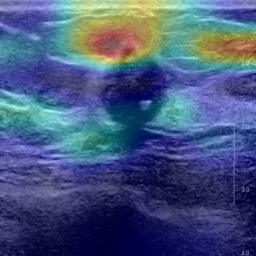

Ultrasonography is an important routine examination for breast cancer diagnosis, due to its non-invasive, radiation-free and low-cost properties. However, it is still not the first-line screening test for breast cancer due to its inherent limitations. It would be a tremendous success if we can precisely diagnose breast cancer by breast ultrasound images (BUS). Many learning-based computer-aided diagnostic methods have been proposed to achieve breast cancer diagnosis/lesion classification. However, most of them require a pre-define ROI and then classify the lesion inside the ROI. Conventional classification backbones, such as VGG16 and ResNet50, can achieve promising classification results with no ROI requirement. But these models lack interpretability, thus restricting their use in clinical practice. In this study, we propose a novel ROI-free model for breast cancer diagnosis in ultrasound images with interpretable feature representations. We leverage the anatomical prior knowledge that malignant and benign tumors have different spatial relationships between different tissue layers, and propose a HoVer-Transformer to formulate this prior knowledge. The proposed HoVer-Trans block extracts the inter- and intra-layer spatial information horizontally and vertically. We conduct and release an open dataset GDPH&GYFYY for breast cancer diagnosis in BUS. The proposed model is evaluated in three datasets by comparing with four CNN-based models and two vision transformer models via a five-fold cross validation. It achieves state-of-the-art classification performance with the best model interpretability.

翻译:超声波分析是乳腺癌诊断的一个重要常规检查,原因是其非侵入性、无辐射和低成本的特性。然而,由于其内在局限性,它仍不是乳腺癌的第一线筛选测试。如果我们能够精确地通过乳房超声图像诊断乳腺癌(BUS),它将是一个巨大的成功。我们提出了许多基于学习的计算机辅助诊断方法,以实现乳腺癌诊断/感官分类。然而,其中多数方法需要事先确定性能模型,然后对ROI内部的跨值进行分类。常规分类支柱,如VGG16和ResNet50等,可以在没有ROI要求的情况下实现有希望的分类结果。但是这些模型缺乏可解释性,从而限制了其在临床实践中的使用。在本研究中,我们提出了一个新的无乳腺癌诊断模型,在超声波图像中进行解释性特征描述。我们利用了先前的解剖学学学知识,即恶性肿瘤和良性肿瘤模型在不同组织层之间有着不同的空间关系,并提议采用状态解析法来编制这一先前的知识。拟议中的HOVer-Trans-Trading-Tradef-trainal Ex-deal-dealal-deal-deal-deal-degraphal-deal-deal-deal-deal-deal-deal disal disal-dal-dal-dal-dal-dal-deal-deal-dal-deal-deal-deal-dal-dal-dal-dal-dal-dal-dal-dal-dal-dal-dal-dal-dal-dal-I-dal-Iversal-dal-Ial-d-d-I-d-d-I-I-I-I-I-I-I-I-I-I-I-I-I-I-I-I-I-I-I-I-I-I-I-I-I-Ial-I-Ial-Ial-I-I-I-I-I-I-I-I-I-I-I-I-I-I-I-I-I-I-I-I-I-I-I-I-I-I-I-I-I-I-I-I-